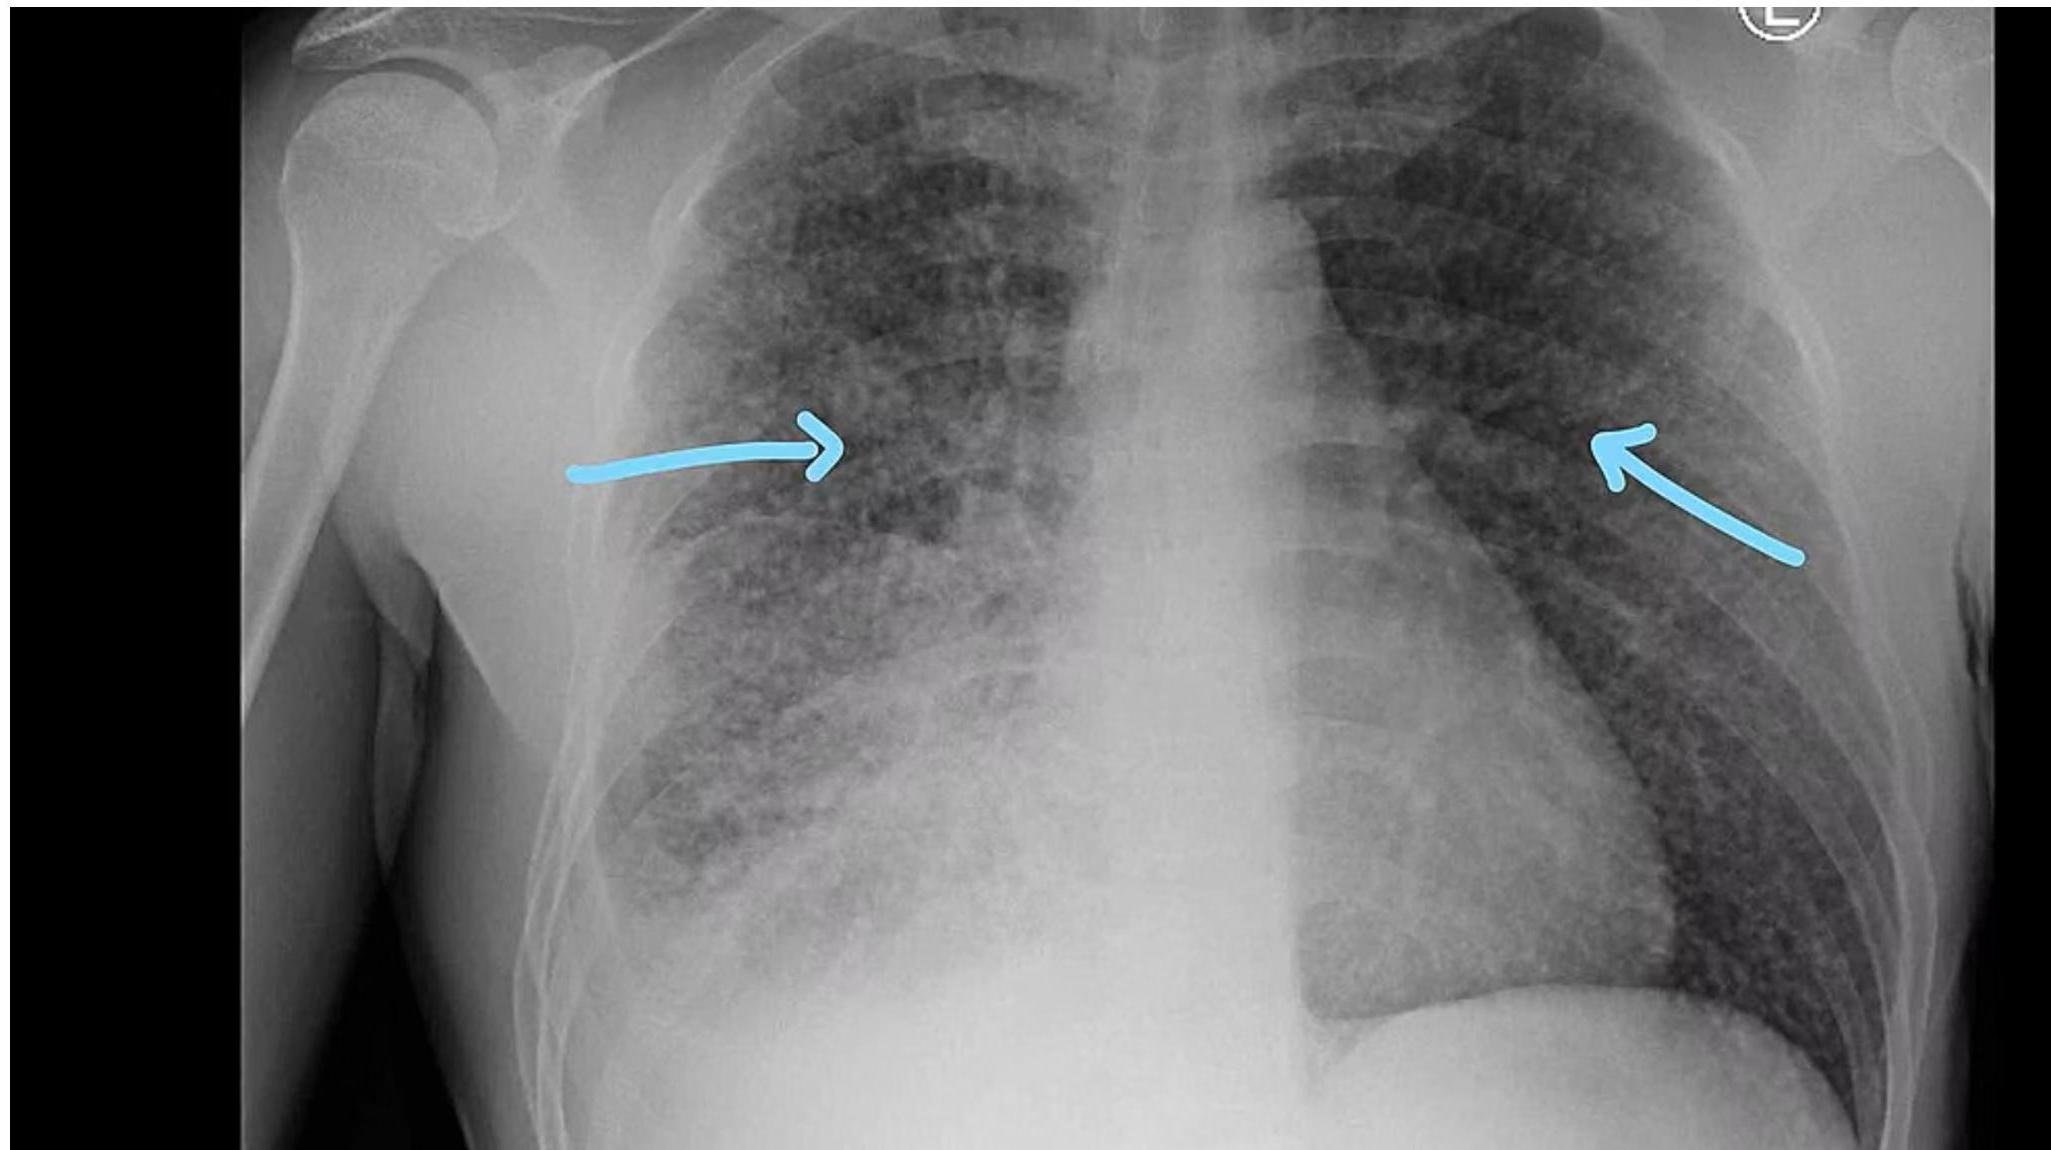

Reactivation Pulmonary Tuberculosis

Typically occurs in adolescents and adults.

1. Location Pattern

Usually confined to the apical segment of upper lobes or superior segments of lower lobes, representing secondary expansion of infection at previously seeded sites.

2. Clinical Features

- Lymphadenopathy: Little lymphadenopathy (distinguishes it from primary TB). -

- Cavitation: Associated with cavitation and endobronchial spread of bacilli.

- Parenchymal: Infiltrates, atelectasis (due to bronchial obstruction), consolidation.

- Advanced: Cavitation (rare in children), miliary pattern.